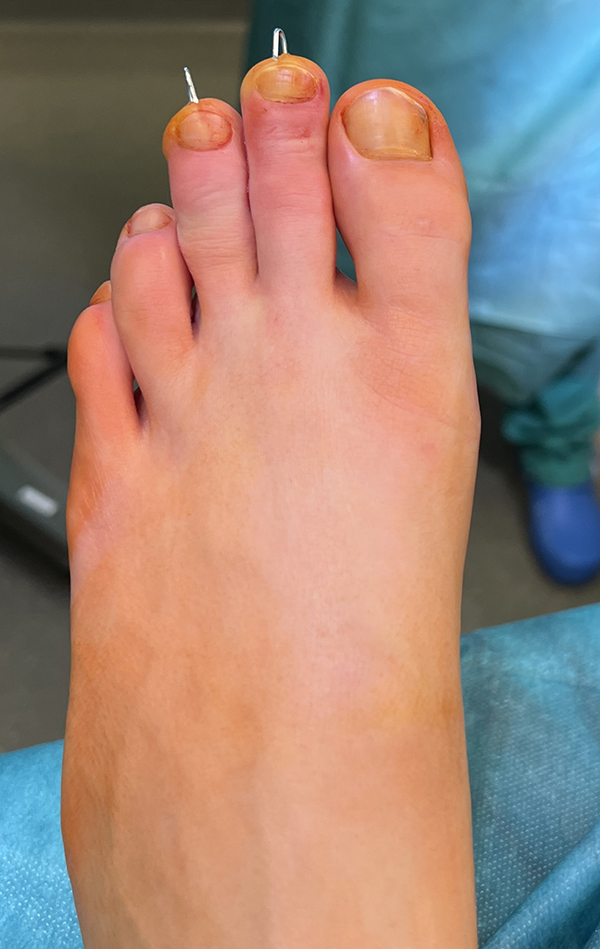

Zehenfehlstellungen

Im Rahmen von sub- oder superduktischen Zehen oder bei Vorhandensein einer Kirner-Deformität werden in unserem Team Kleinzehenkorrekturen entweder komplett oder inkomplett und sowohl am Grundglied kombiniert als auch am Mittelglied durchgeführt (Abb. 20).

Abb. 20 a-d: Krallenzehen mit subluxierter Gelenkstellung. Präoperatives Röntgenbild d. p. (a), intraoperative Nadelmarkierung für die entsprechenden Osteotomien (b); postoperatives Röntgenbild mit einer Multilevel-Korrektur der Zehen (c) und klinischer postoperativer Verlauf (d). In der letzten Aufnahme zeigt sich gut die bereits korrigierte Zehenstellung am rechten und die noch nicht versorgten Zehen am linken Fuß.

Die Osteotomien werden ganz dem Bedarf angepasst. Es lassen sich über Verkürzung, Derotation und bei Bedarf auch Translation enorme Korrekturen erreichen. Für ein verbessertes Sehnenzuggleichgewicht kombinieren wir die Osteotomien bei Bedarf mit einem Beugesehnentransfer nach Girdlestone-Taylor (Abb. 10 und 21).

Werden komplette Osteotomien an den Zehen durchgeführt, fädeln wir die Osteotomien mit einem 1.2 oder 1.4 mm Kirschner-Draht auf, damit die einzelnen Fragmente nicht verkippen (Abb. 22).